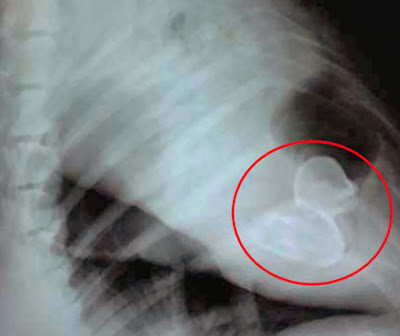

In this picture, the rubber duck swallowed by a dog is helpfully circled, in case you couldn't spot it.